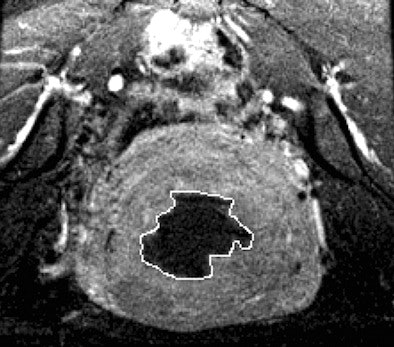

| Above, T2-weighted axial MR image of a hypointense fibroid in a 46-year-old patient before MR-guided focused ultrasound surgery. Below, T1-weighted gadolinium-enhanced axial MR image of the same fibroid immediately after treatment. |